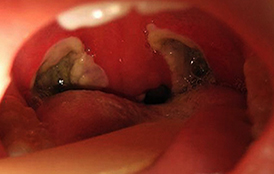

Восстановление после удаления миндалин — длительный и иногда болезненный процесс, требующий строгого соблюдения рекомендаций врача. На третьи сутки реабилитации пациенты могут заметить усиление боли при глотании. Это связано с образованием фибринового налета на прооперированных участках, где в течение следующих 5-6 дней начнет формироваться новый слой эпителиальной ткани.

Увеличение регионарных лимфоузлов и субфебрильная температура — признаки регенерации, а не воспаления слизистой горла.

Белесоватый налет на месте удаленных миндалин начинает исчезать уже на шестой день после тонзиллэктомии. Спустя 5-6 дней ниши гланд очищаются от фибриновых нитей, и к 21-23 дню они полностью покрываются новым эпителием. У детей процесс восстановления проходит быстрее, поэтому они легче переносят операции по сравнению со взрослыми и пожилыми пациентами.